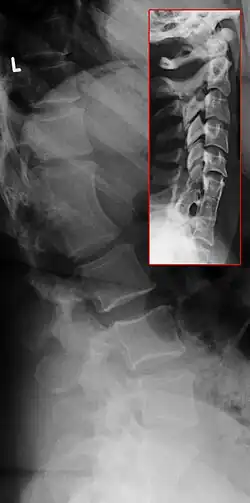

Le syndrome de Klippel-Feil ou SKF (en anglais, Klippel-Feil syndrome ou KFS) est une condition caractérisée par un défaut de segmentation des somites cervicaux, résultant en une fusion congénitale de vertèbres cervicales.

Aujourd'hui, n'importe quelle fusion congénitale d'au moins deux vertèbres est considérée comme une manifestation du syndrome de Klippel-Feil.

Une classification est proposée indépendamment dès 1919 par André Feil et Maurice Klippel. Ils ont décrit des patients avec un pterygium colli, une réduction de la gamme de mouvement dans la colonne cérébrale et une base des cheveux anormalement basse. Feil par la suite a proposé une classification du syndrome dans trois catégories:

- Type 1 - Fusion de C2 et C3 avec occipitilisation de l'atlas. McRae en 1953 a complété la définition du Type 1.

- Type 2 - Longue fusion en dessous de C2 avec une jonction anormale occipito-cervical. Le problème dans ce cas peut se situer au niveau thoracique. Il s'agit de la forme la plus répandue du syndrome[4].

- Type 3 - Une ouverture de l'espace situé entre deux sections vertébrale fusionnée. Le type 3 peut être aisément distingué des type 1 et 2, par la présence d'une inflexion au niveau du segment ouvert.